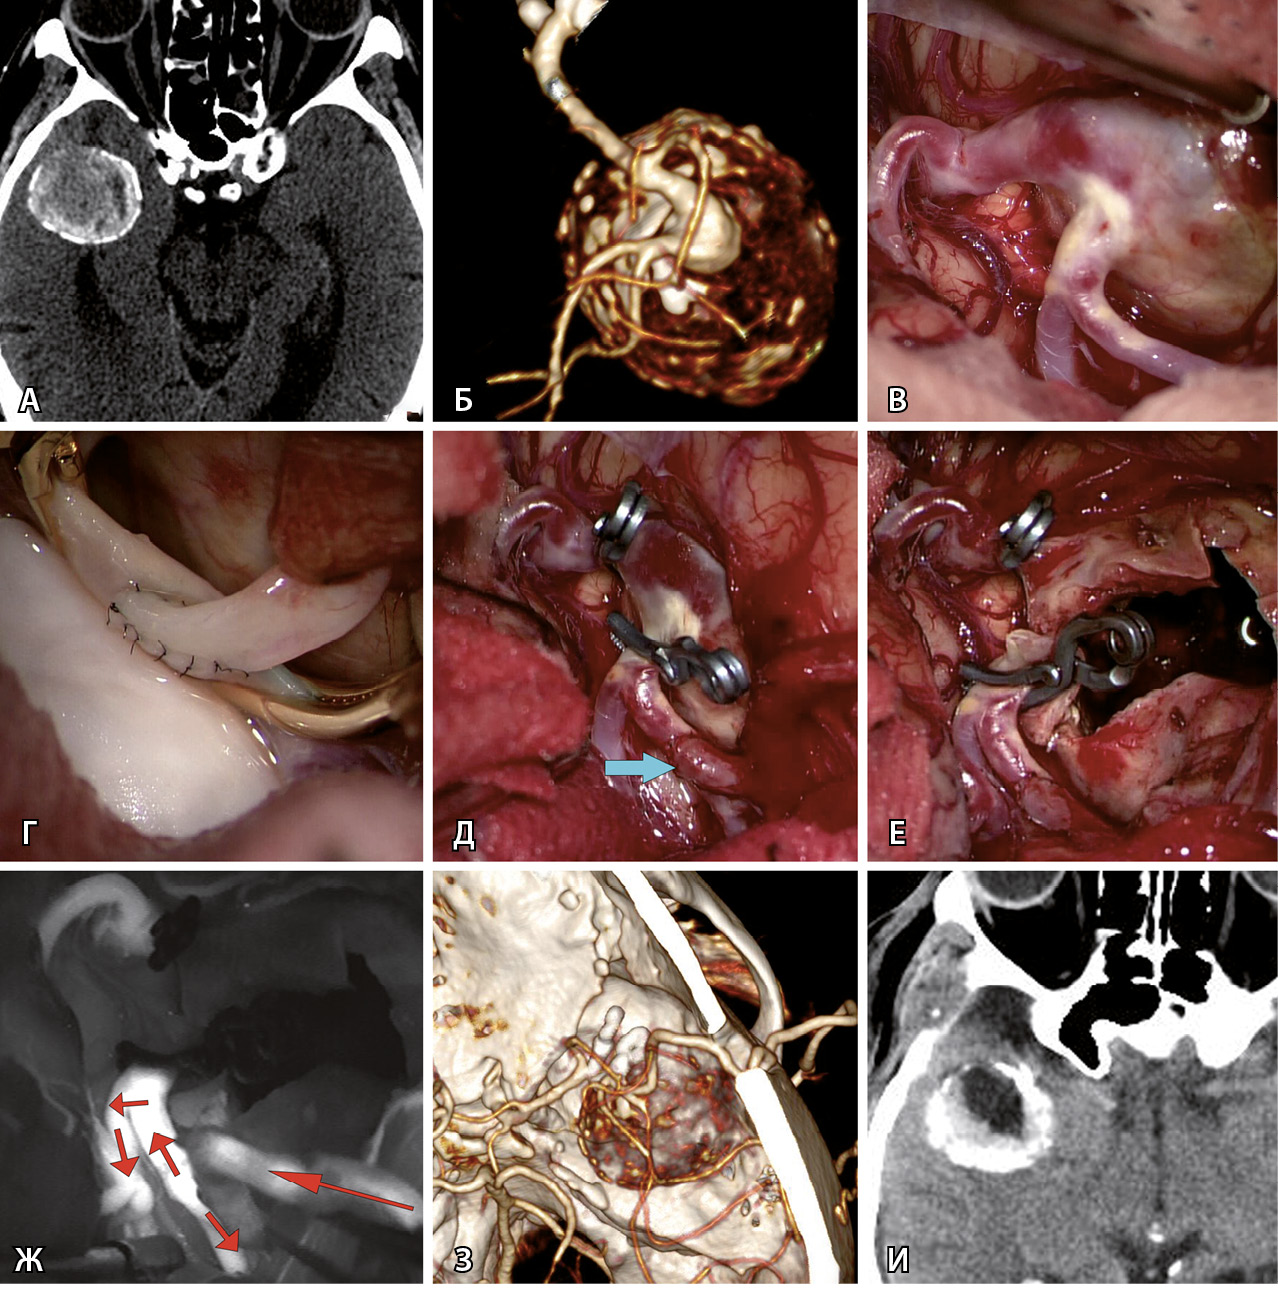

Наиболее частой операцией было клипирование шейки (КШ) – в половине (50,9%) всех случаев. Клипирование аневризмы одной клипсой произведено только в 5 наблюдениях. У остальных 23 пациентов выполнено множественное клипирование с наложением от 2 до 7 клипс (в среднем – 3,2 ± 1,5). Пример клипирования гигантской аневризмы приведен на рис. 1. У 17 больных перед КШ проведена тромбэктомия из полости гигантской аневризмы. У 6 больных тромбэктомию делали после КШ.

Рис. 1. Клипирование гигантской аневризмы средней мозговой артерии (СМА) справа у пациентки Г., 59 л. А – при компьютерной томографической ангиографии определяется гигантская аневризма трифуркации СМА справа (желтыми стрелками указаны три М2-ветви СМА справа, белой стрелкой указана припаянная к телу аневризмы передняя височная артерия). Б – интраоперационное фото: отмечается выступающее в сильвиеву щель тело аневризмы СМА справа. В – после наложения временной клипсы на М1-сегмент справа (указан черной стрелкой) мешок аневризмы релаксировал, что позволило выделить и визуализировать три М2-ветви (указаны желтыми стрелками). Г – длинная изогнутая клипса наложена на шейку аневризмы. Д – после клипирования наблюдается небольшой остаточный участок шейки аневризмы (указан стрелкой) у теменного М2-сегмента. Е – наложение на остаточный участок шейки аневризмы маленькой изогнутой клипсы. Ж – результат клипирования шейки аневризмы двумя клипсами. З – контрольная церебральная ангиография в прямой проекции. И – контрольная церебральная ангиография в боковой проекции